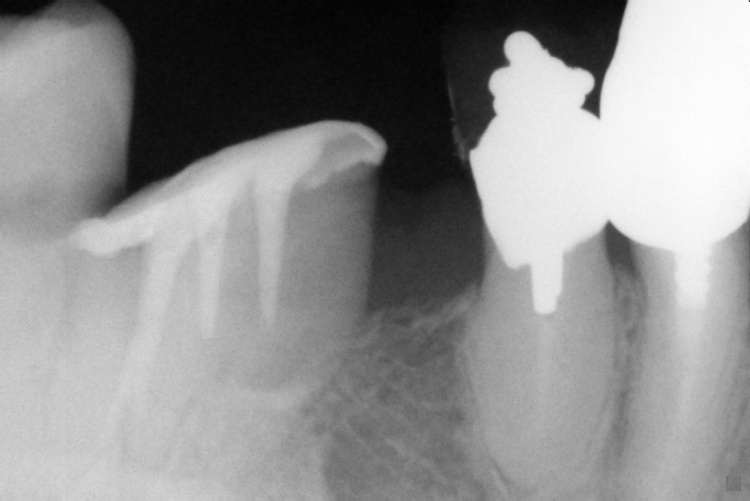

IO000001.jpg

2020-07-28 13:22 74K